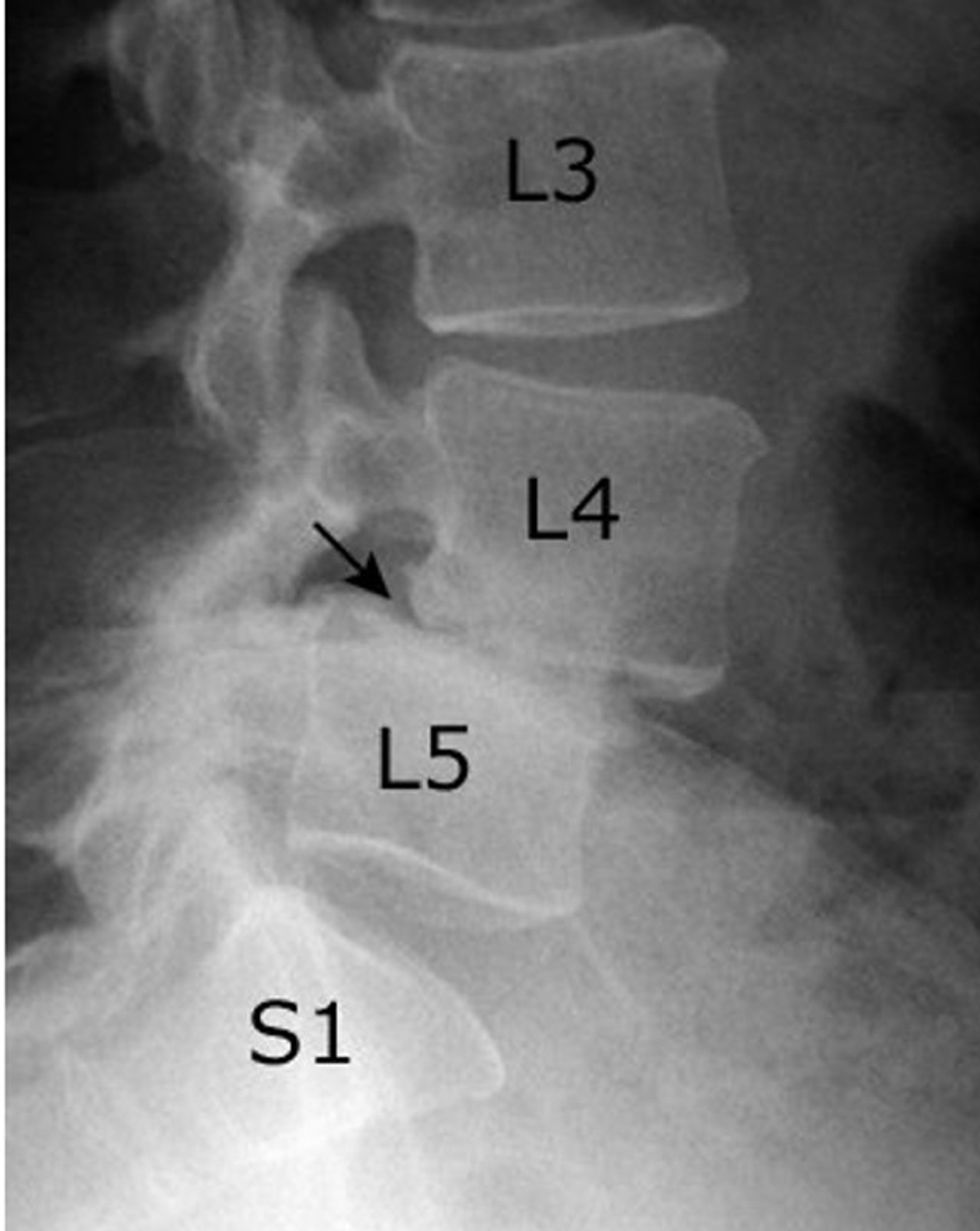

Spondylolisthesis definohet si rrëshqitje e përparme apo e pasme e unazës krahasuar me tjetrën nën të, me apo pa instabilitet spinal.

Varësisht nga shkalla e rrëshqitjes së unazave në planin sagital, sipas Meyerding (1932):

Grada 1 - ≤ 25% të diametrit vertebral

Grade 2 - 25-50%

Grade 3 - 50-75%

Grade 4 - 75-100%

Spondyloptosis – mbi 100%

Rëntgen standard në dy drejtime, rtg në dinamikë - përkulje nga përpara apo nga prapa dhe anash.